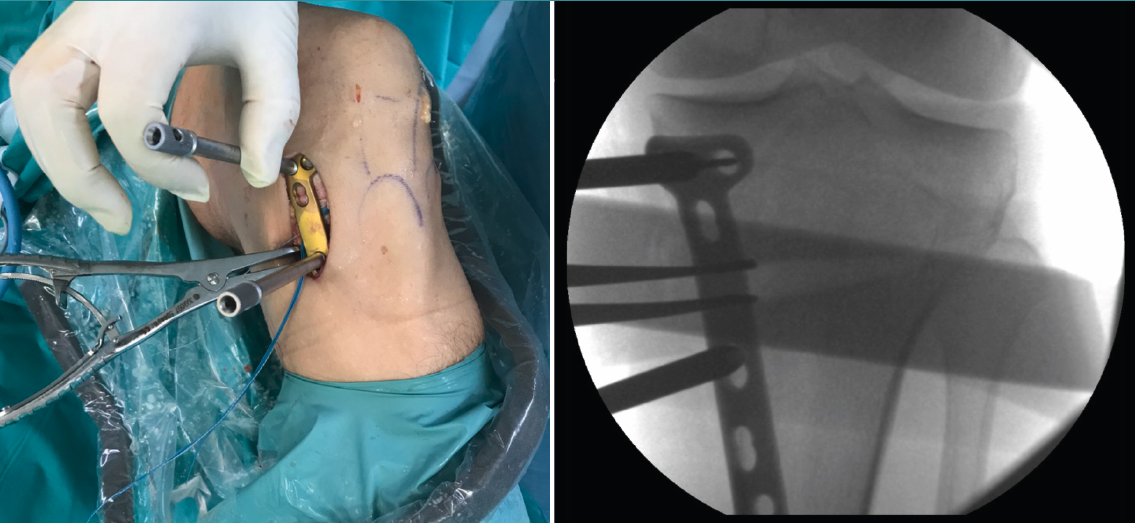

Posteriormente, bajo control radioscópico, se realiza la osteotomía apoyando la sierra por debajo de la aguja guía, llegando hasta 1 cm de la cortical lateral. Se introducen los escoplos para abrir la osteotomía (Figura 4). El primer escoplo, el más ancho, se introduce primero para comprobar el corte completo de la cortical posterior. Seguidamente, se coloca el medidor del ángulo de apertura (Figura 5A) y, a continuación, se introduce el distractor en la parte posterior de la osteotomía, evitando así un aumento de la PTP (Figura 5B). En este momento, se puede introducir en la apertura de la osteotomía el aloinjerto o sustituto óseo. Los autores utilizan aloinjerto óseo cuando la apertura es mayor de 10°. Antes de colocar y fijar la placa de osteotomía, se realiza el túnel tibial utilizando las herramientas artroscópicas clásicas (Figuras 6A y 6B). Al realizar una osteotomía biplanar, el corte es suficientemente distal como para permitir brocar el túnel tibial de la RLCA sin dificultades.

Una vez hecho el túnel tibial, se introduce la plastia y se fija a nivel femoral y tibial (Figura 7). Si se utiliza una plastia de isquiotibiales, los autores recomiendan una fijación femoral cortical de suspensión regulable, dejando unos milímetros para el ajuste final después de la colocación de la placa de osteotomía. Una vez fijada la plastia, se procede a la colocación de la placa de osteotomía TomoFix® (Synthes, Oberdorf, Switzerland) para la tibia proximal medial (Figura 8). En la mayoría de los casos el tornillo más anterior coincide con el túnel tibial de RLCA, motivo por cual no se coloca (Figura 9).

Figura 6. A: colocación de la aguja guía para realizar el túnel tibial; B: brocado del túnel tibial. Se observa el espacio metafisario suficiente para realizar el túnel tibial, sin interferencias con la osteotomía.